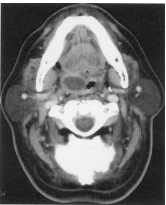

73 46 歲男性,主訴右側耳鳴。根據此張 MRI,T2WI,引起右側耳鳴最可能的原因是:

(A) NPC 引起右耳積水乳突炎(mastoiditis) (B)細菌性右耳積水乳突炎(bacterial mastoiditis) (C)病毒性右耳積水乳突炎(viral mastoiditis) (D)乳突膽脂瘤(mastoid cholesteatoma)